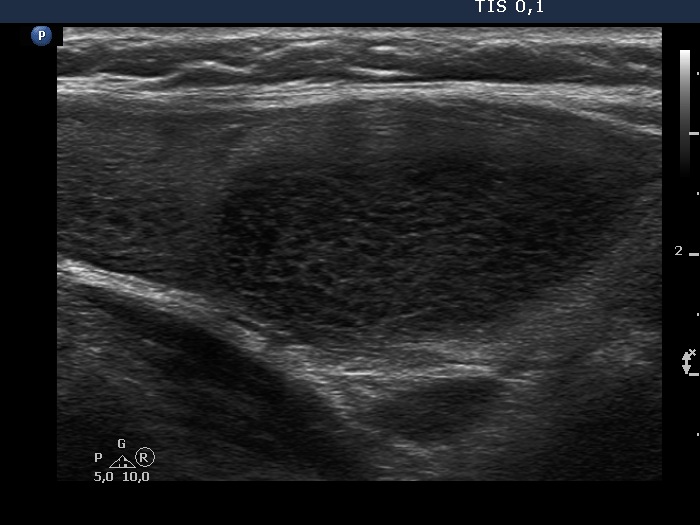

Second examination 3 years later (second, fourth and sixth rows of images):

Ultrasonography. Compared with the previous examination, both the number and the size of discrete lesions in the thyroid have increased.